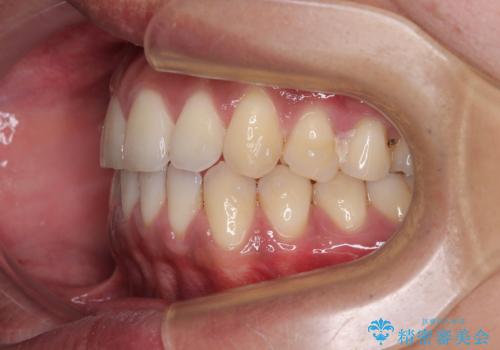

診察したところ、上下顎前歯部に軽度の叢生(ガタつき)が認められます。

目立たない装置を希望されたのでインビザライン ライトパッケージで治療を行うことになりました。